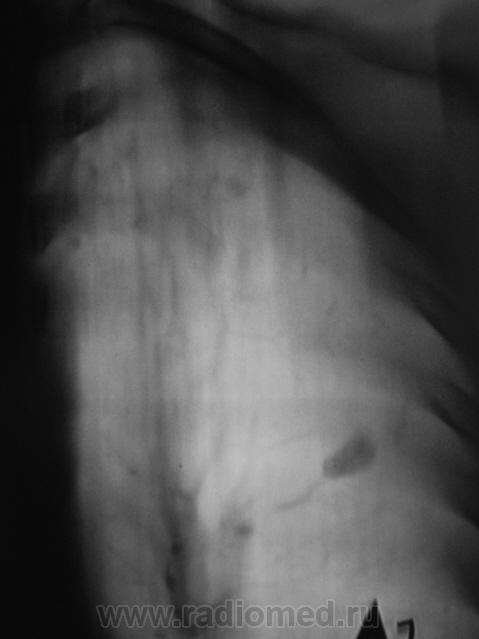

Рентгенограмма.

ТОМОГРАФИЯ.